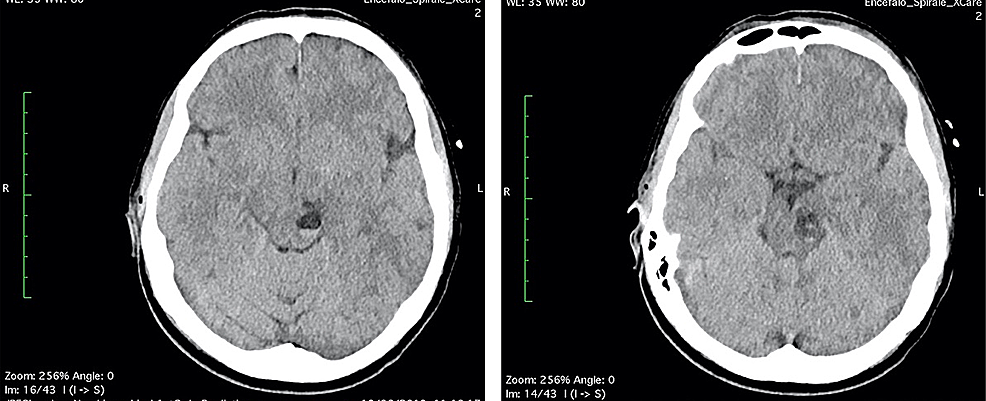

The first day after surgery, the patient was transfunded for hemoglobin 6.8 g/dL (normal range 12-16 g/dL), referring to scalp surgery. She complained headache, vertigo, nausea and diplopia, reflecting an involvement of the brainstem and the oculomotor nerves. A second CT and brain MRI with IV contrast were performed: CT scan showed a fluid-fluid level, with enlargement of left cerebral peduncle and a slight mass effect (Figure 2). MRI scan confirmed the same findings of fluid-fluid level, with enlargement of left cerebral peduncle and a slight mass effect; no contrast enhancement was observed: these findings were referred to enlargement of VRSs with post-traumatic bleeding. Neither SAH nor intracerebral hematomas were revealed (Figure 3). No neurosurgery was indicated but only clinical and imaging follow up.